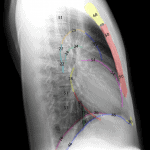

* Giải phẫu X-quang Ngực – Bụng: Tim phổi – Ổ bụng.